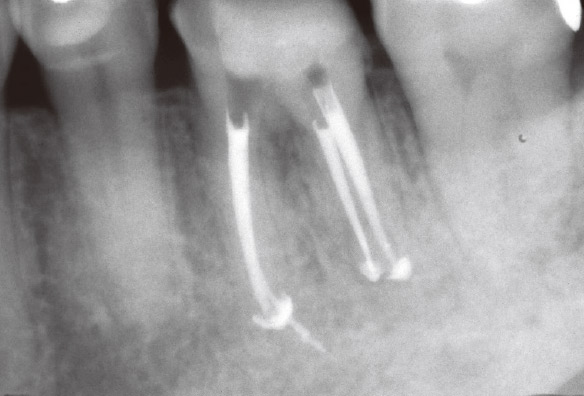

私が4年前に再根管治療を行った1が再発してしまいました。マラソンの時にズンズン響くというのですが、口腔内に瘻孔や深いポケットなどの異常所見は見られませんでした。デンタルでもはっきりした根尖部透過像は確認できませんでしたが(図3a)、CBCTでは一目瞭然でした(図3b,c,d)。矢状断と水平断から病変は口蓋側に広がっており、根尖部の骨が厚く皮質骨は破壊されずに維持されていることが確認されました(図2、図3b,d)。これがデンタルでは病変が確認できなかった理由でした。感染源は根尖部の口蓋側寄りに存在すると推測され、側枝の可能性も疑われました。マイクロサージェリーを提案しましたが、患者さんの強い希望により、メタルボンドクラウンを外さずにコンベンショナルな再治療を行うことになりました。ガッターパーチャ(GP)除去後、マイクロエキスカで根尖孔周囲の感染源を徹底的に除去し洗浄した後、MTAにて根管充填しました(図3e)。根充後4ヵ月で根尖部の骨が再生されていました(図3f,g,h)。この症例もまた、CBCTを撮像しなければ、皮質骨まで破壊が進行し瘻孔ができるまで、デンタルでの病変の検出は困難だったと考えられます(図2)。腫脹し、ポケットから排膿してきた場合は歯周病や破折との鑑別も必要になり、病態はより複雑化していくことが想像できます。自分の行った治療の再発時に口腔内に異常所見がなく、デンタルでも病変が確認できなければ、咬合調整して消極的な経過観察をしてもおかしくはありません。CBCTにより早期に病変を発見できたため、患者さんとの信頼関係も維持することができました。

図3a 患者さんはマラソン時にズンズン響くと訴えていたが、根尖部に透過像はみられなかった。

図3b CBCT矢状断。根尖部に口蓋側に広がる病変が確認された。

図3c CBCT前頭断。デンタルでは確認できなかった病変がはっきり認められた。

図3d CBCT水平断。病変は口蓋側のやや近心寄りに広がっていた。

図3e 根管充填後のデンタルX線写真。MTAにて根管充填。

図3f CBCT矢状断(根充後4M)。根尖部に骨が再生してきていた。

図3g CBCT前頭断(根充後4M)。根尖病変は消え、骨の再生が確認できた。

図3h CBCT水平断(根充後4M)においても、骨の再生が確認できた。